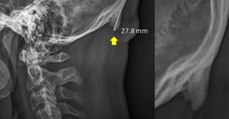

Non, le smartphone ne fait pas pousser de "corne" osseuse sur le crâne. Voici pourquoi